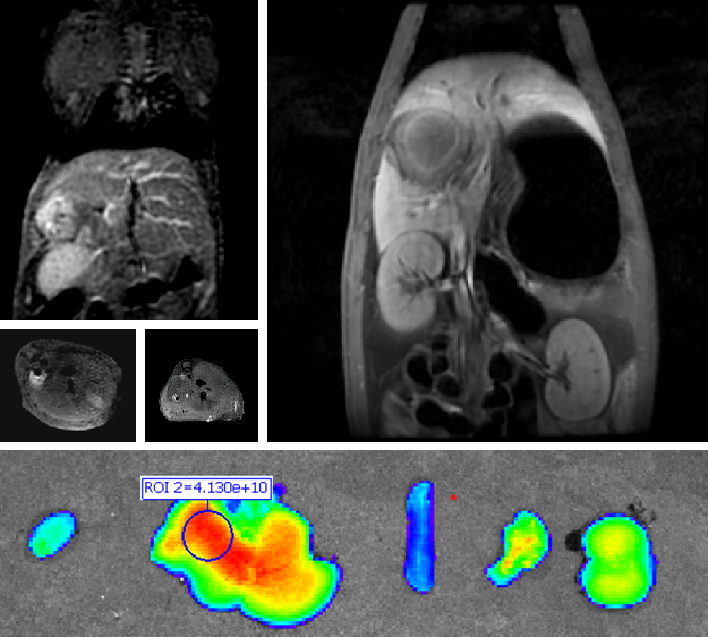

创新双模态造影剂(PL002)

yl23411永利集团自主研发的双模态造影剂PL002,已经获得美国FDA临床试验批件。PL002的研制首次提出通过整合磁共振技术,弥补现有荧光染料假阳性率高、透射深度有限等的短板,进而提升手术的精确性,降低手术过程中的风险,是全球首个获批临床试验的荧光/磁共振双模态造影剂。本项目预示着海南普利在造影剂领域的长期投入,并致力于开展独具特色的差异化国际化创新发展路径。